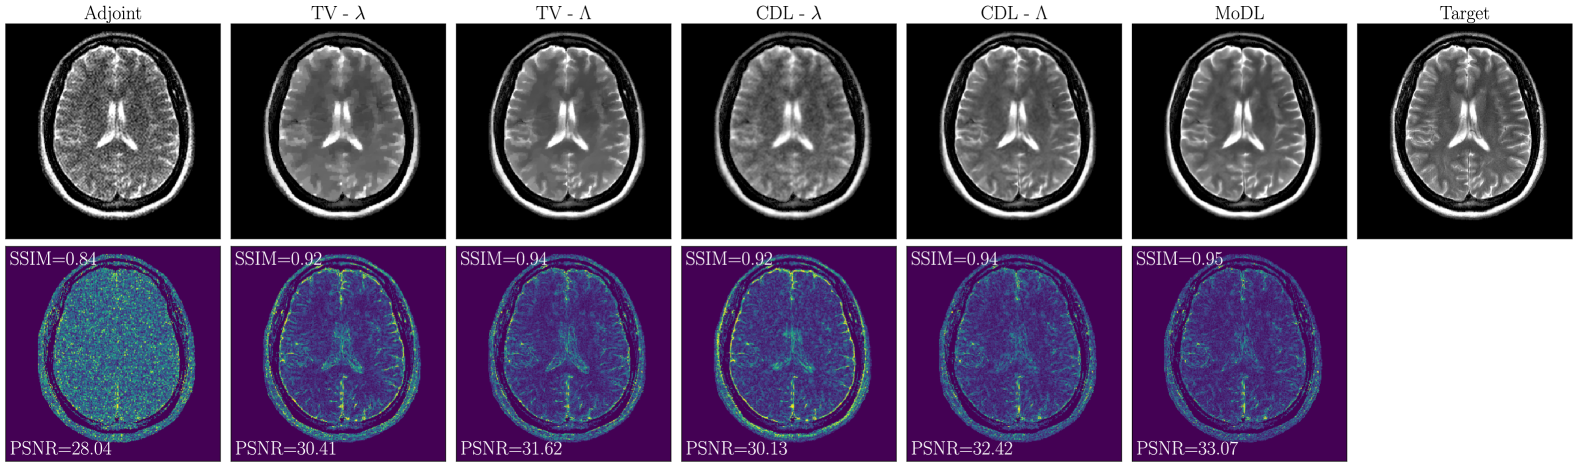

Figure 3 shows an example of images reconstructed for a noise level of . All methods successfully improved upon the adjoint-based reconstruction, which heavily suffers from noise and blurring artifacts. The methods employing only scalar regularization values exhibit larger errors at the boundaries and are clearly outperformed by both TV- [7] and the proposed CDL-, which employ learned regularization parameter maps and yield results comparable to the deep learning-based method MoDL [17]. Although similar in terms of SSIM and PSNR, the investigated CDL- yields more anatomically accurate images in contrast to TV-, which, despite the spatially adaptive regularization, still tends to exhibit some piece-wise constant structures. Finally, the investigated CDL- exhibits a high visual similarity when compared to MoDL.

Figure 4 summarizes the results obtained on the test set in terms of SSIM and PSNR. The methods involving only scalar regularization parameters (TV- and CDL-) are outperformed by their corresponding counterparts (TV- and CDL-) involving the learned adaptive spatial regularization, which are competitive even when compared to the deep learning-based MoDL [17].